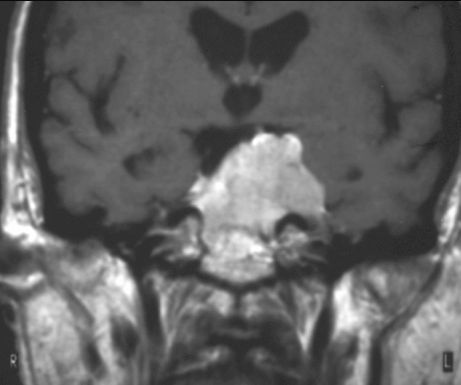

OPONIAK

MRI